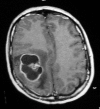

Unusual manifestations of primary Glioblastoma Multiforme: A report of three cases

Background: Brain tumors, especially high-grade gliomas, can present with focal or generalized signs due to mass effect, parenchymal infiltration and destruction. In general, at the time of diagnosis, tumors could cause common neurological symptoms and major clinical signs depending on their localization. In rare instances, brain tumors colud be manifested with unusual symptoms.

Case description: WE DESCRIBE THREE CASES PRESENTING WITH UNUSUAL CLINICAL SYMPTOMS: ulnar neuropathy, vertigo and syncope attacks. Microscopic total tumor excision was done and histopathological analysis revealed that these tumors were glioblastoma multiforme. Both external beam radiotherapy and chemotherapy were given as adjuvant treatments.